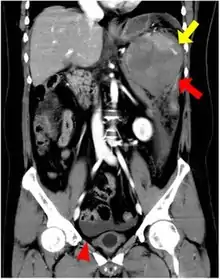

CT scan of an accessory spleen (circular object in center of image) between the spleen and left kidney. | |

An accessory spleen is a small nodule of splenic tissue found apart from the main body of the spleen. Accessory spleens are found in approximately 10 percent of the population[1] and are typically around 1 centimetre in diameter. They may resemble a lymph node or a small spleen. They form either by the result of developmental anomalies or trauma.[2] They are medically significant in that they may result in interpretation errors in diagnostic imaging[2] or continued symptoms after therapeutic splenectomy.[1] Polysplenia is the presence of multiple accessory spleens rather than one normal spleen.

If splenectomy is performed for conditions in which blood cells are sequestered in the spleen, failure to remove accessory spleens may result in the failure of the condition to resolve.[1] During medical imaging, accessory spleens may be confused for enlarged lymph nodes or neoplastic growth in the tail of the pancreas,[5] gastrointestinal tract, adrenal glands or gonads.[2]